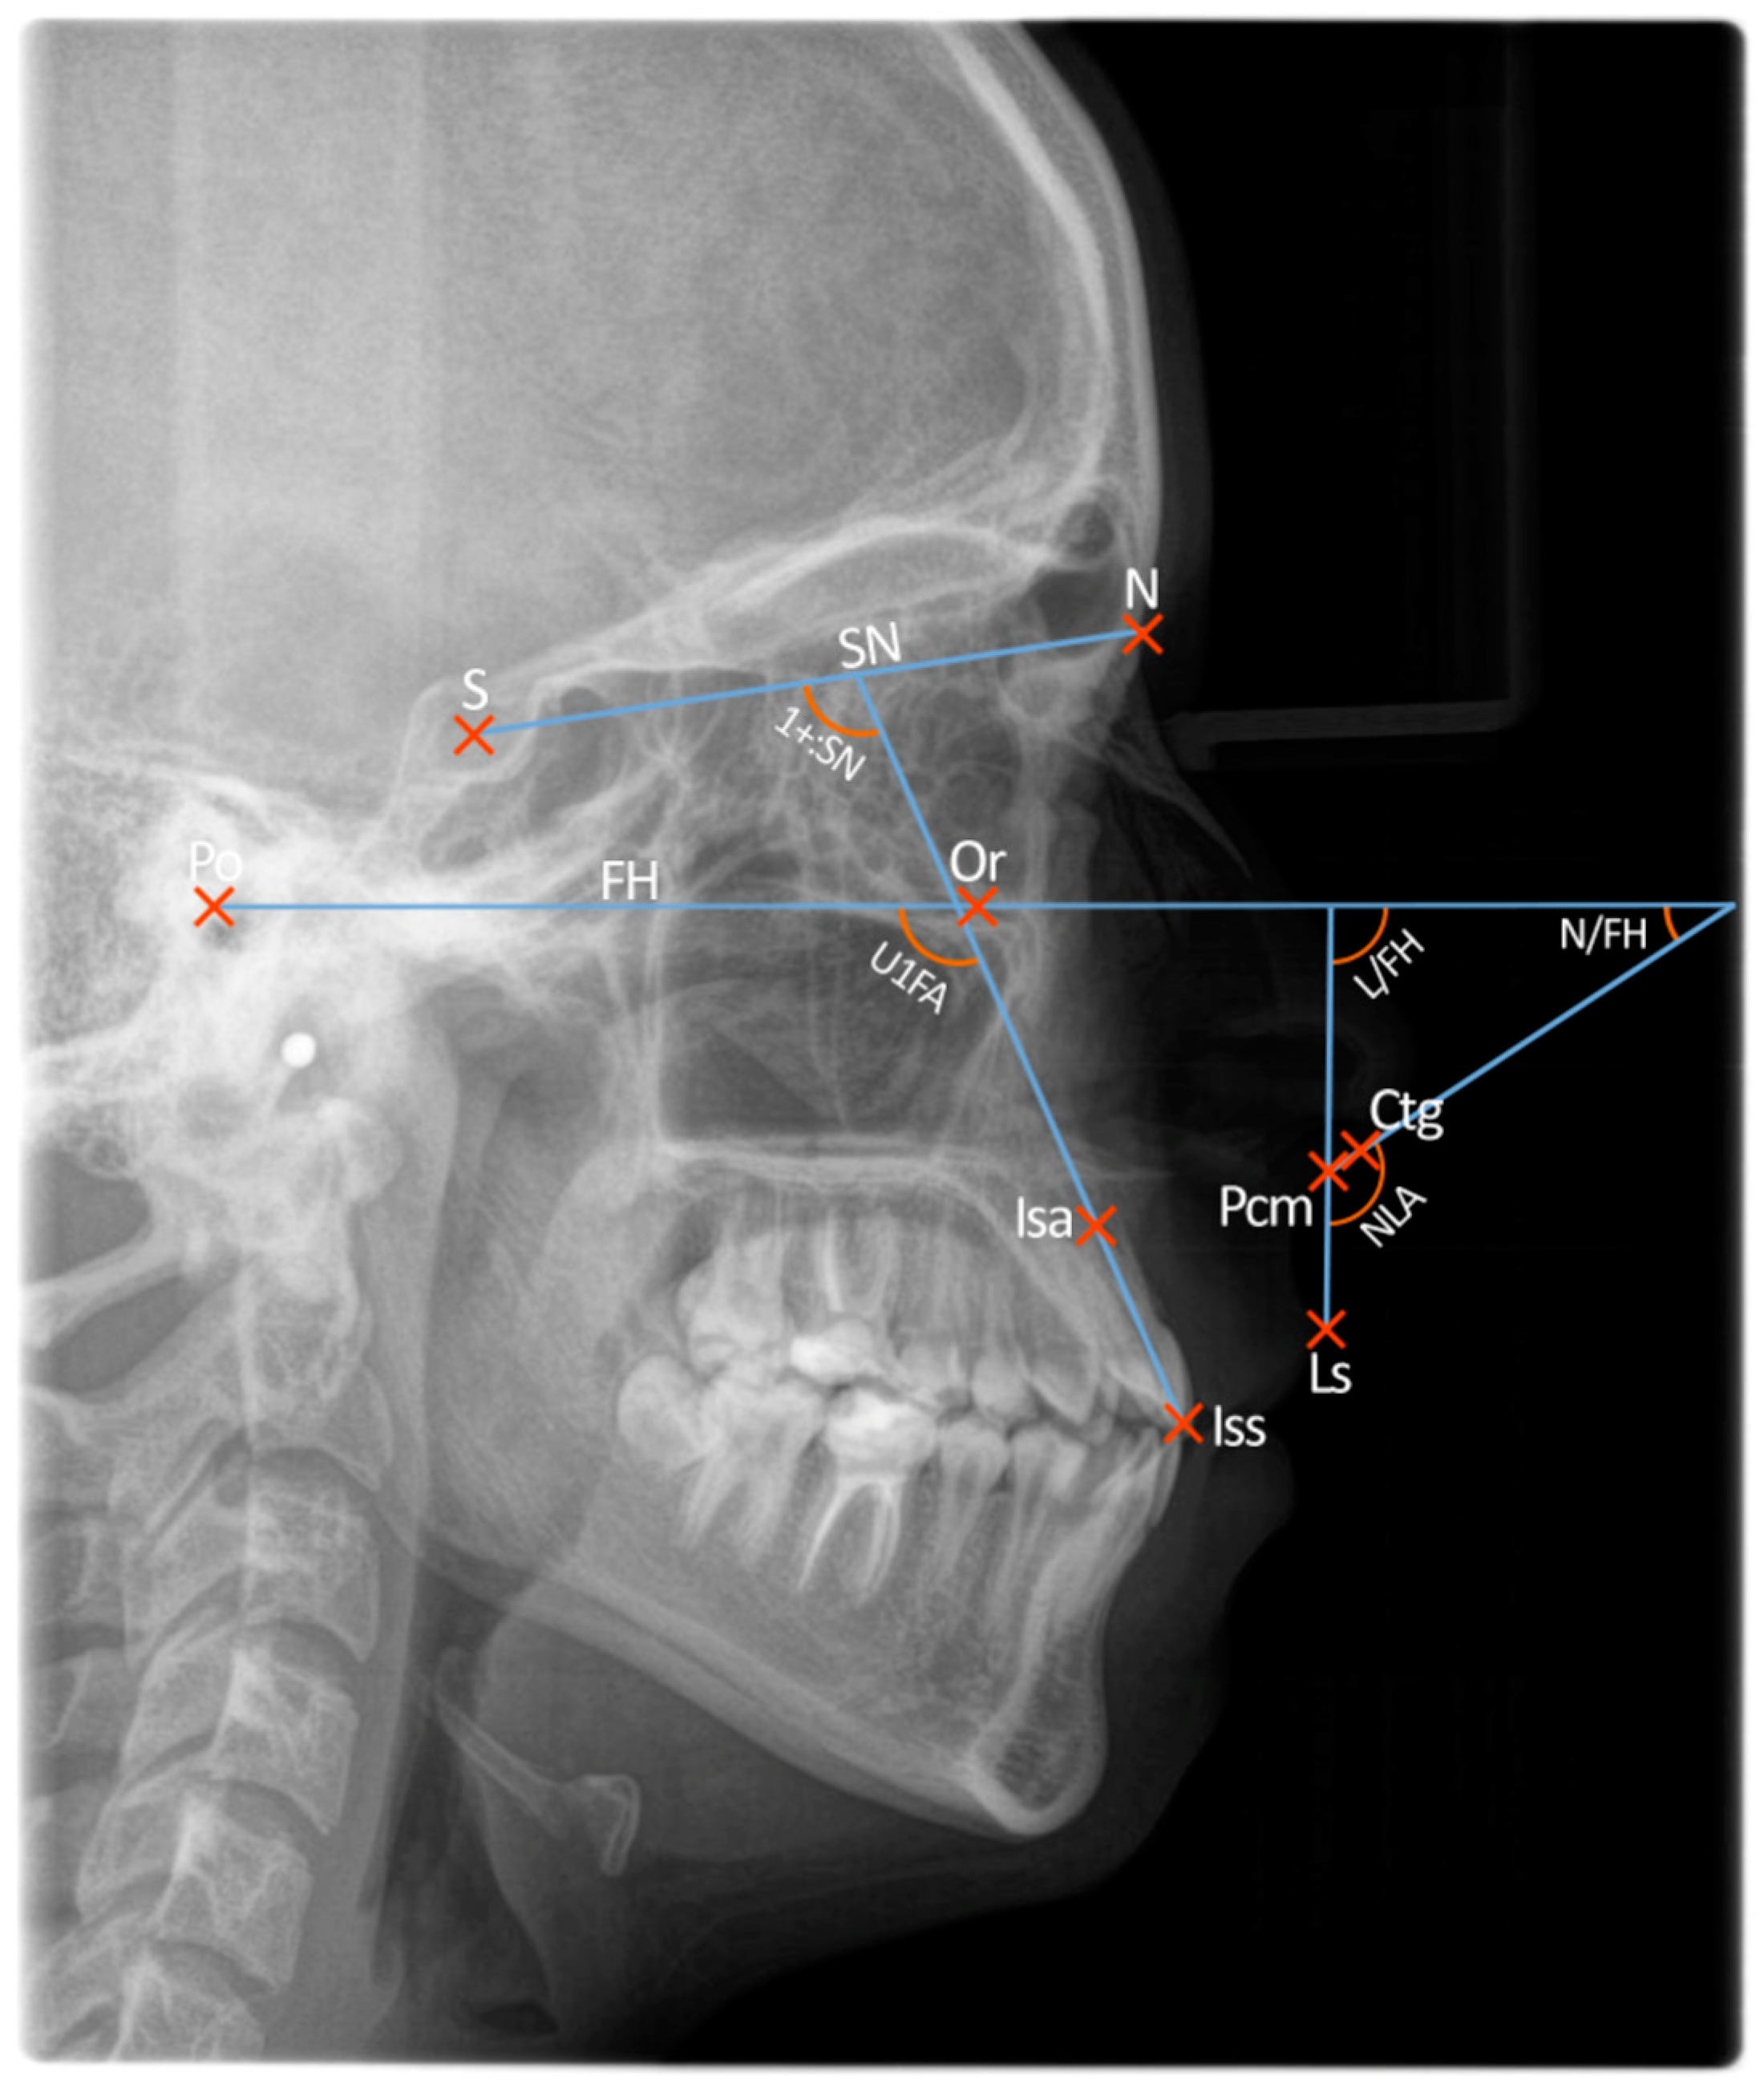

- Sella—S

- Nasion—N

- Porion—Po

- Orbitale—Or

- Incisal edge of the upper central incisor—Iss

- Root apex of the upper central incisor—Isa

- Labrale superius—Ls

- Posterior columella—PCm

- Columella—ctg

- Nasolabial angle (NLA)

- Upper incisor to sella-nasion line (1+:SN)

- Upper incisor to Frankfort horizontal plane (U1FA)

- Upper lip to Frankfort horizontal plane (L/FH)

- Lower border of the nose to Frankfort horizontal plane (N/FH)

- The most posterior point of the lower border of the nose, at which it begins to turn inferiorly to merge with the philtrum of the upper lip, was located and called the posterior columella point, or PCm.

- A tangent was drawn from PCm anteriorly along the lower border of the nose at its approximate middle third; the angle of this line extending anteriorly and intersecting the Frankfort horizontal plane was considered the relative inclination of the nose and termed lower nose to FH angle, or N/FH (nasal component of the nasolabial angle). If this line representing the lower border of the nose was parallel to the Frankfort horizontal plane, it was measured at 0°. In some cases, the tip of the nose was turned so far down that the tangent to the lower border of the nose intersected the Frankfort horizontal plane posteriorly. In this instance, a negative value of the anteroinferior angle (N/FH) formed at this intersection was recorded.

- A line drawn from PCm to the labrale superius (Ls), when extended superiorly, intersects the Frankfort Horizontal plane and forms an angle considered the relative inclination of the upper lip and termed upper lip to FH angle, or L/FH (the labial component of the nasolabial angle).